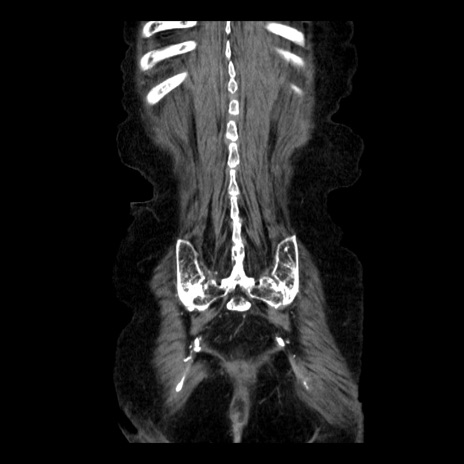

症例14(冠状断像)

【症例】 90歳代女性

【主訴】 腹痛・嘔吐

【現病歴】今朝から左側腹部痛を認めた。 経過観察していたが、嘔吐を認めたため来院。

【既往歴】 子宮癌術後

【身体所見】 意識清明、BP 127/54mmHg、P 98bpm Sp02 95%(RA)、BT 35.8°C、腹部平坦・軟腸ぜん動音聴取良好、右下腹部圧痛(+) 反跳痛なし

【データ】WBC 9800、CRP 0.46